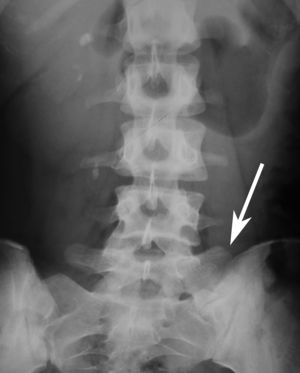

ضيق الفقرة القطنية